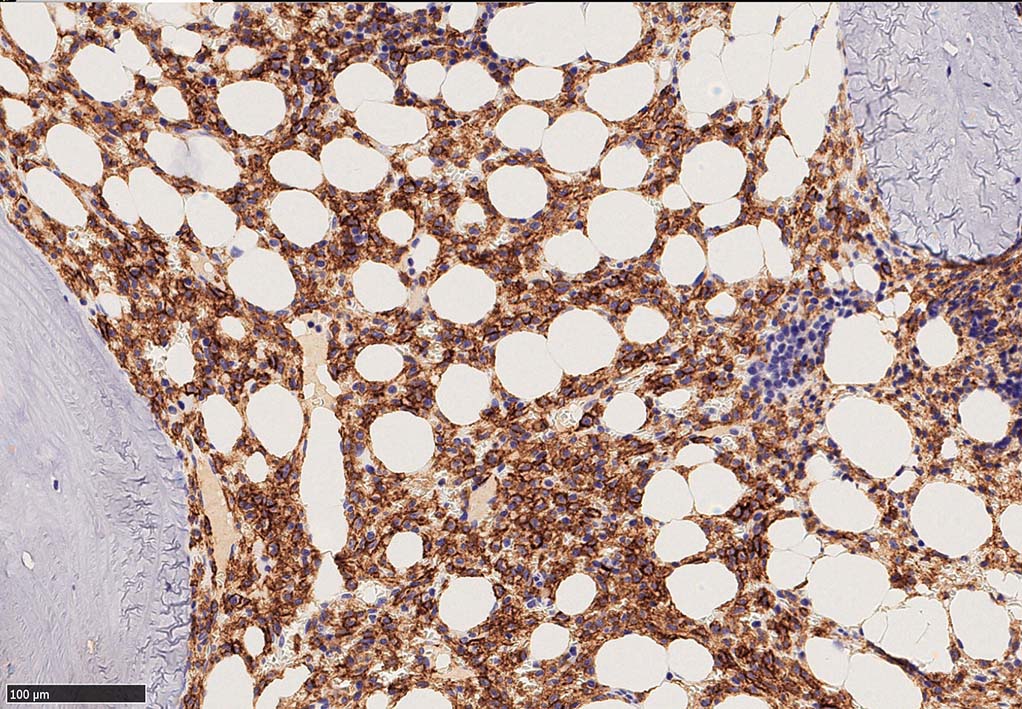

BRAF V600E変異タンパクの免疫染色(山梨医大 大石先生に染色していただきました. ベンタナ, Optiview)

増殖細胞はCD20(相変わらずべったり染まる), CD19, PAX5陽性 CD25陽性.